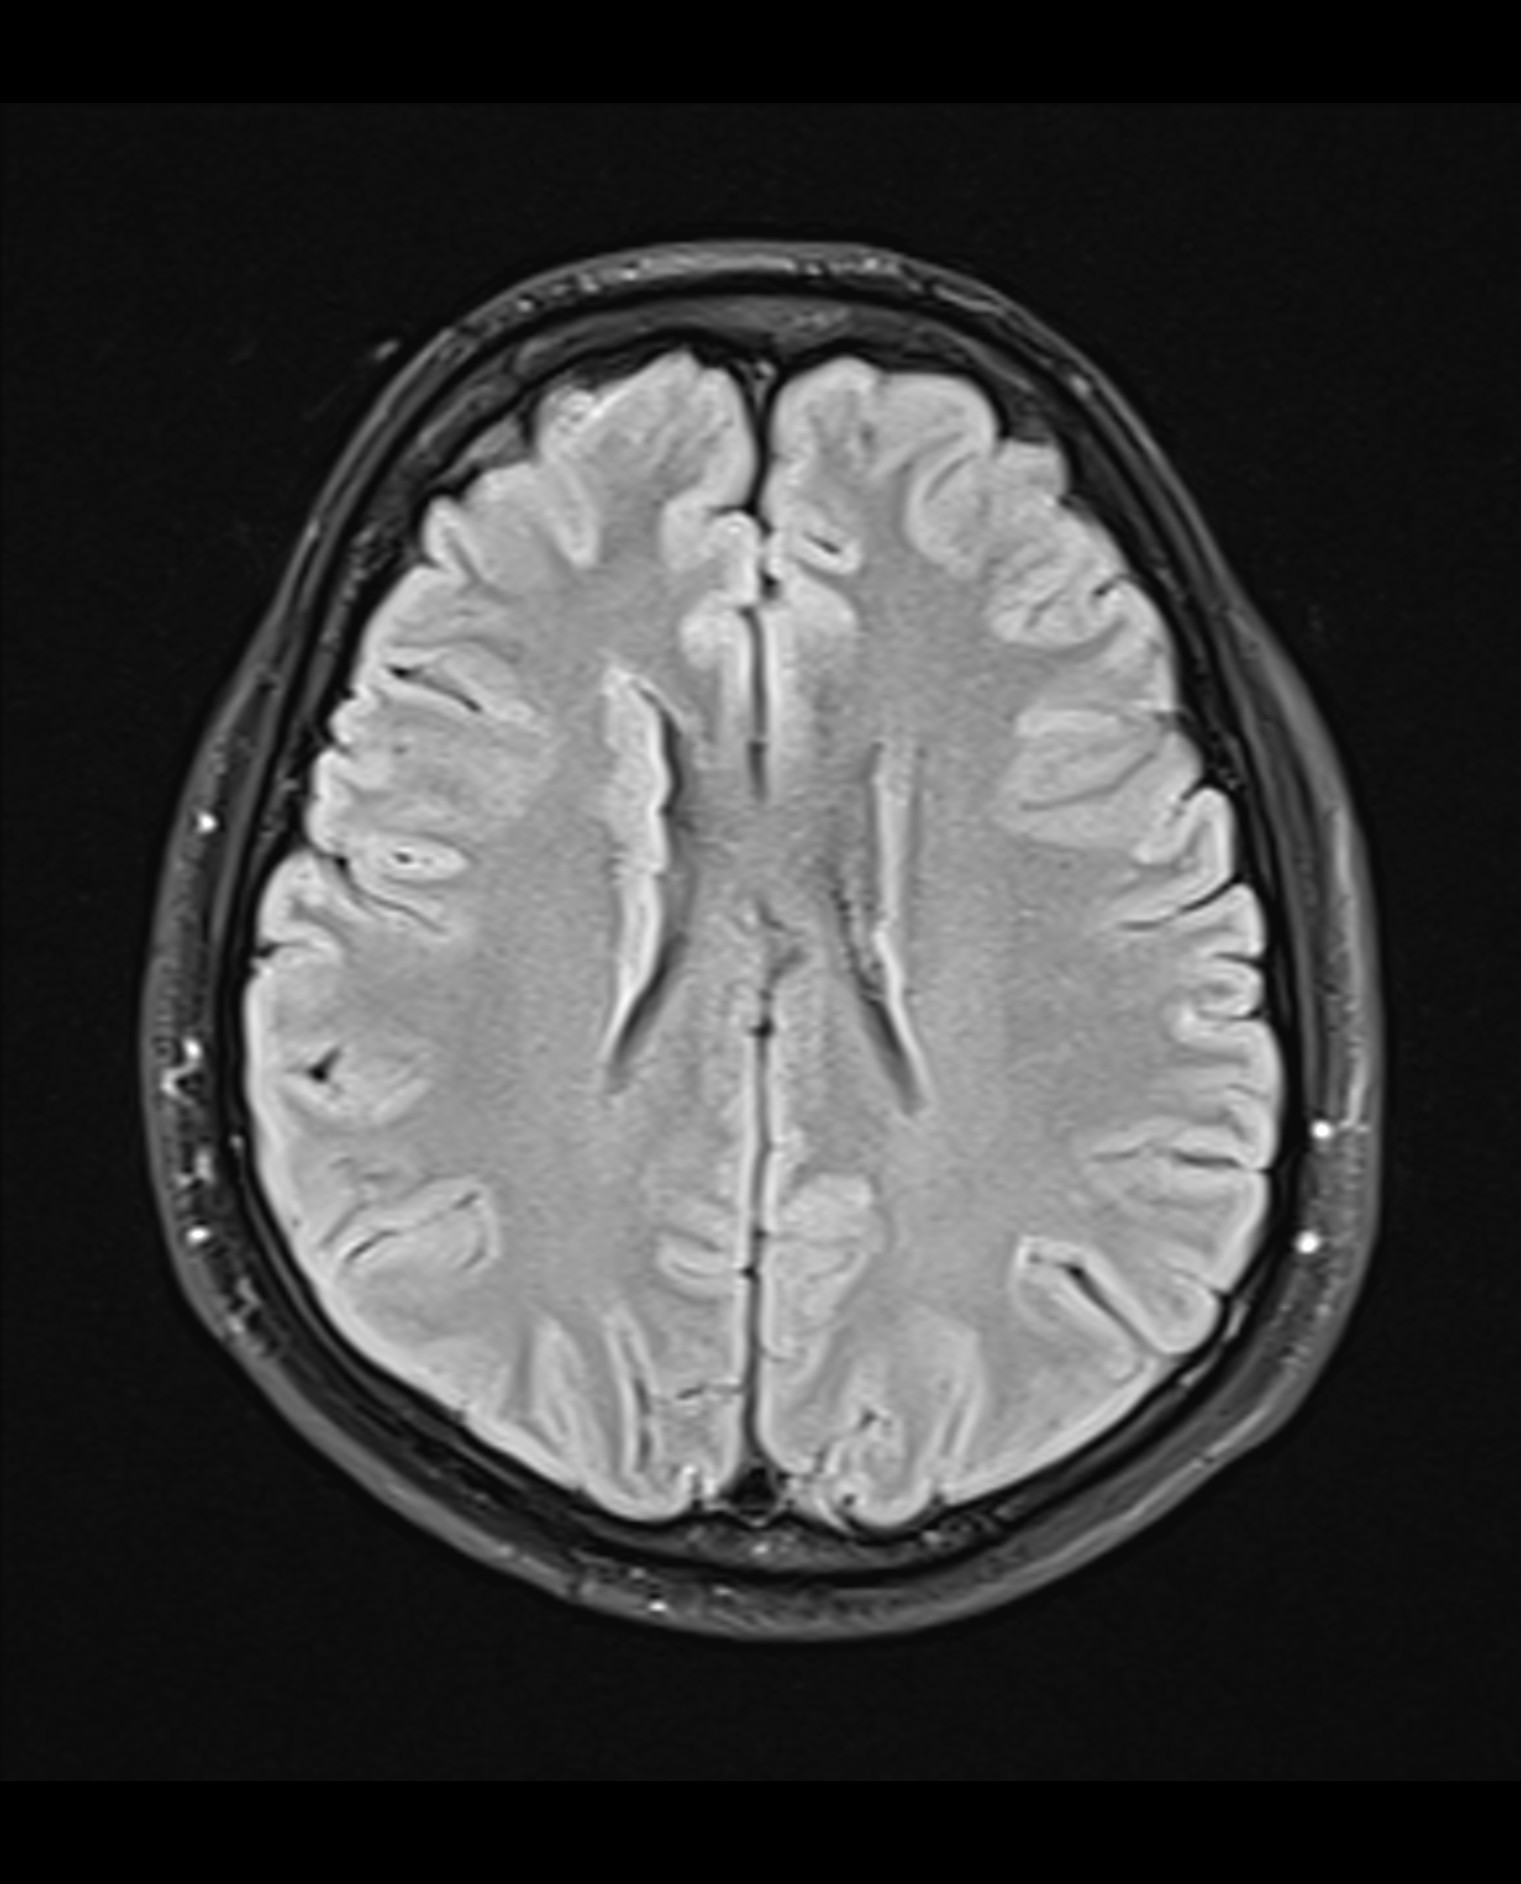

Fazekas grades. Лейкоареоз головного мозга мрт. Перивентрикулярный лейкоареоз мрт. Лейкоареоз Фазекас. Лейкоареоз на кт.

Fazekas grades. Лейкоареоз головного мозга мрт. Перивентрикулярный лейкоареоз мрт. Лейкоареоз Фазекас. Лейкоареоз на кт.

Fazekas grades. Лейкоареоз головного мозга мрт. Перивентрикулярный лейкоареоз мрт. Перивентрикулярный лейкоареоз головного мозга на кт. Лейкоареоз Fazekas 1 что это.

Fazekas grades. Лейкоареоз головного мозга мрт. Перивентрикулярный лейкоареоз мрт. Перивентрикулярный лейкоареоз головного мозга на кт. Лейкоареоз Fazekas 1 что это.

Fazekas grades. Лейкоареоз на кт. Лейкоареоз головного мозга мрт. Перивентрикулярный лейкоареоз. Перивентрикулярный лейкоареоз мрт.

Fazekas grades. Лейкоареоз на кт. Лейкоареоз головного мозга мрт. Перивентрикулярный лейкоареоз. Перивентрикулярный лейкоареоз мрт.